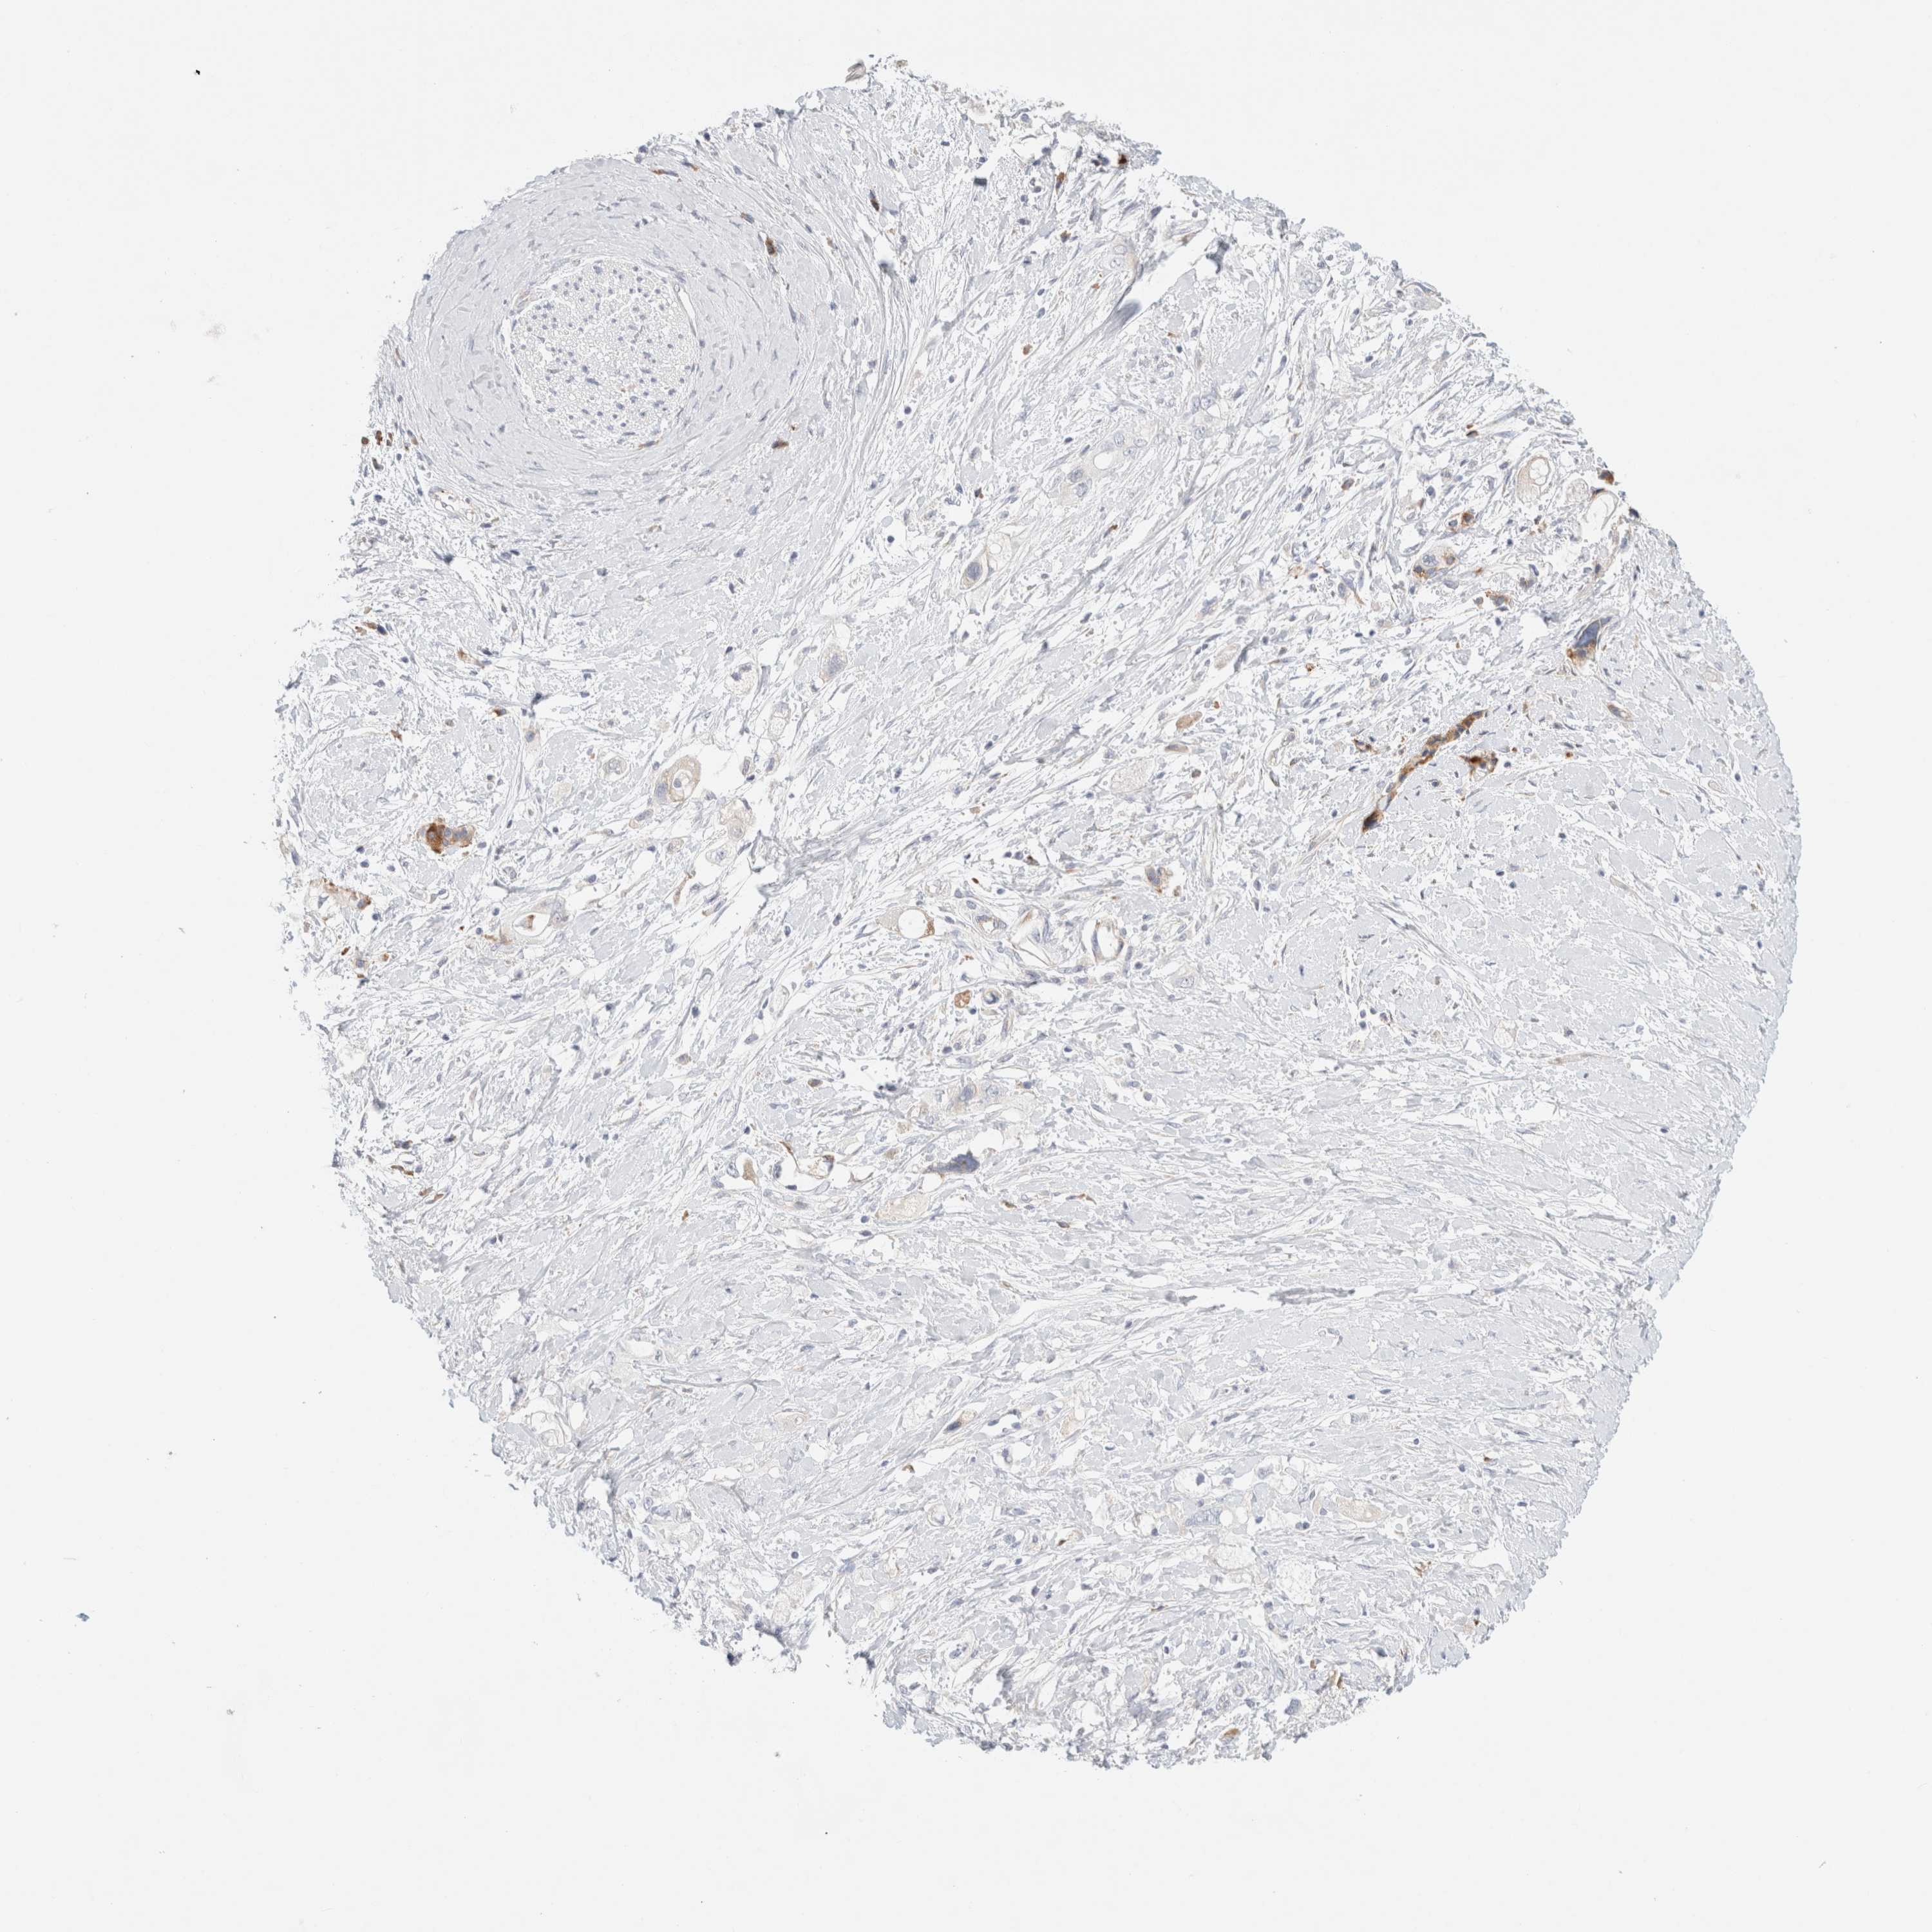

PANCREATIC CANCER - Protein expressioni

A mouse-over function shows sample information and annotation data. Click on an image to view it in a full screen mode. Samples can be filtered based on level of antibody staining by selecting one or several of the following categories: high, medium, low and not detected. The assay and annotation is described here.

Note that samples used for immunohistochemistry by the Human Protein Atlas do not correspond to samples in the TCGA dataset.

Antibody stainingi

Antibody staining in the annotated cell types in the current human tissue is reported as not detected, low, medium, or high, based on conventional immunohistochemistry profiling in selected tissues. This score is based on the combination of the staining intensity and fraction of stained cells.

Each image is clickable and will lead to virtual microscopy that enables deeper exploration of all samples and also displays staining intensity scores, fraction scores and subcellular localization as well as patient and tissue information for each sample.

Antibody HPA026488

Antibody HPA028425

Antibody CAB011203

Staining

High

Medium

Low

Not detected

Intensity

Strong

Moderate

Weak

Negative

Quantity

>75%

75%-25%

<25%

None

Location

Nuclear

Cytoplasmic/membranous

Cytoplasmic/membranous,nuclear

Adenocarcinoma, NOS

Adenocarcinoma, metastatic, NOS